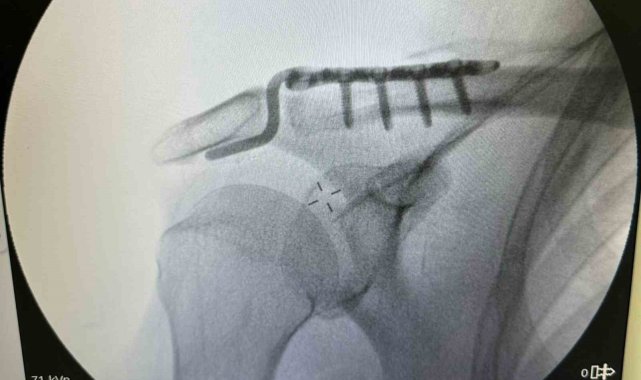

Batman'da, tenis oynarken omuz çıkığı yaşayan 64 yaşındaki Mehmet Şerif Rençber, ileri yaş nedeniyle ameliyat olamayacağı, kendiliğinden iyileşeceği cevabı olmasına rağmen başka bir doktorun özel plak kullanarak ameliyat etmesiyle sağlığına kavuştu.64 yaşındaki Mehmet Şerif Rençber, tenis oynarken omzunun üzerine düşmesiyle çıkık yaşandı. Rençber, tedavi için gittiği başka doktorlardan ileri yaşı nedeniyle ameliyat edilemeyeceği, kendiliğinde iyileşmesi gerektiği cevabını aldı. Batman Eğitim ve Araştırma Hastanesi Ortopedi ve Travmatoloji Uzmanı Dr. Mehmet Yavuz Başer'e başvuran Rençber, burada kullanılan özel plakla sağlığına kavuştu.Dr. Başer, hastanın 64 yaşında omuz çıkığı nedeniyle kendilerine başvurduğunu söyledi. Kendisi, arkadaşlarıyla tenis oynarken omuz üzerine düşme sonrası omuzunda bir çıkık geliştiğini belirten Başer, "Normalde bu omuz çıkığını genç hasta grubunda görebiliyoruz. Hastamız ileri yaş olmasına rağmen aktif spor yapan bir hastamız. Bize başvurduğunda omuz eklemi yerinde değildi. Hastanın kemik yapısına tam uyumlu, nadir kullanılan özel bir plak ile başarılı bir ameliyat gerçekleştirdik. Daha sonra biz de ameliyat kararı verdik. Ameliyatında daha çok gençlerde kullanılan nadir, özel şekilli, çengel bir plak kullandık. Daha sonra filmlerini de çekip kontrol ettikten sonra hastamızın ameliyatını başarılı bir şekilde tamamladık. Başarılı ameliyatın ardından hemen fizik tedavi sürecini başlattık. Hastamız bugünden itibaren yavaş yavaş omuz hareketlerini yapabilecek hale geldi. Kol askısından bir an önce kurtulacak ve hastamız en geç 2-3 haftaya kadar eski omuz hareketlerine ağrısız kavuşmasını bekliyoruz" dedi.Daha önce başvurduğu doktorların ileri yaşı nedeniyle ameliyatın mümkün olmayacağını ve kendiliğinden iyileşmesi gerektiğini söylediklerini belirten Rençber ise, "Benim gibi emekli olan arkadaşlarımla tenis oynarken omuz üstüne düştüm. Düşmem münasebetiyle omuzdaki açılma çok büyüktü. Birkaç doktora gittim ve Bu ameliyatın mümkün olamayacağını, 25 yaşına kadar olan hastaları genelde ameliyat yaptıklarını söylediler. 'Yaşının ileri yaş grubunda olduğunuz için dokunmuyoruz. O kendi kendine iyileşir' dediler. Sonra da Doktor Mehmet Yavuz Bey'e geldim. Mehmet Yavuz Bey durumu inceledi. Dedi ki, 'yapabilirim.' Bunda inşallah sıkıntı yaşamasın dedi şimdi başarılı bir ameliyat oldum, çok memnun kaldım. Bayağı ilgilendi. Ameliyat sonrası en ufak bir sancı, bir sıkıntı görmedim ve yaşamadım. Ameliyat sonrası bile omuzum neredeyse eskisi gibi hareket edebiliyorum, kısıtlılığım ilk gün bile ciddi şekilde azaldı" şeklinde konuştu.

Tenis oynarken omuz çıkığı yaşayan 64 yaşındaki hasta, kullanılan özel plakla sağlığına kavuştu

Batman'da, tenis oynarken omuz çıkığı yaşayan 64 yaşındaki Mehmet Şerif Rençber, ileri yaş nedeniyle ameliyat olamayacağı, kendiliğinden iyileşeceği cevabı olmasına rağmen başka bir doktorun özel plak kullanarak ameliyat etmesiyle sağlığına kavuştu.